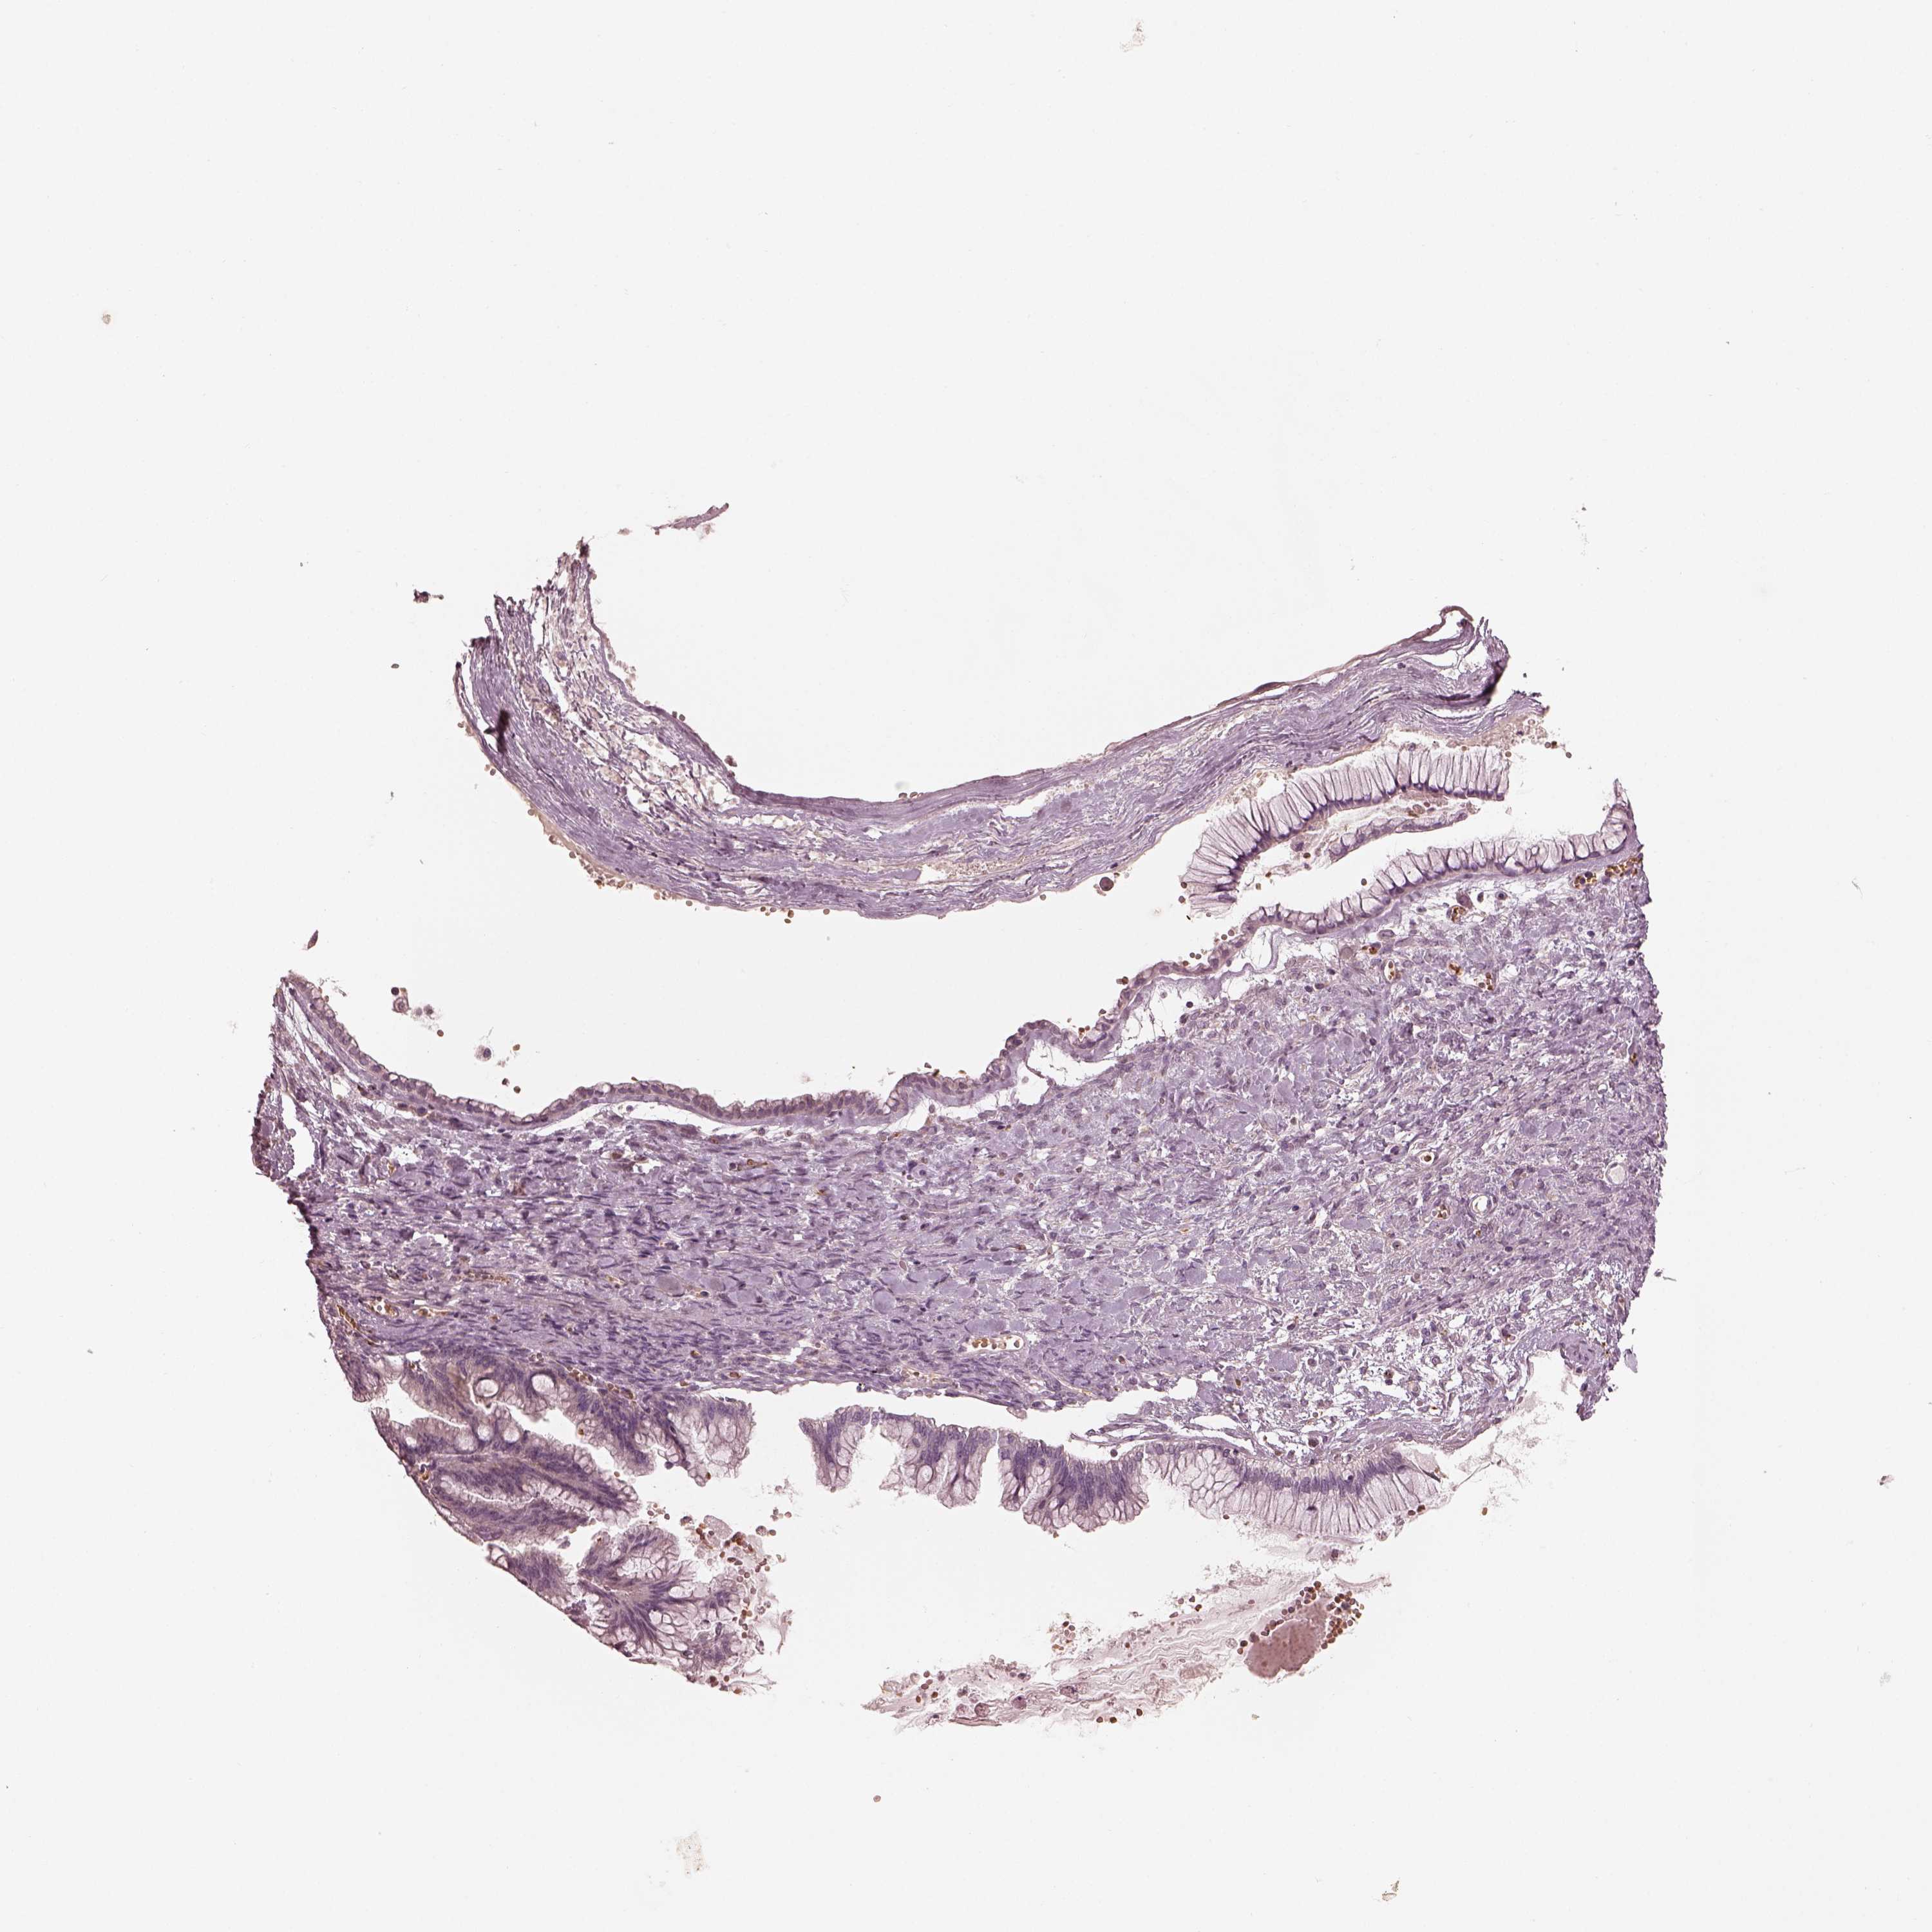

OVARIAN CANCER - Protein expressioni

A mouse-over function shows sample information and annotation data. Click on an image to view it in a full screen mode. Samples can be filtered based on level of antibody staining by selecting one or several of the following categories: high, medium, low and not detected. The assay and annotation is described here.

Note that samples used for immunohistochemistry by the Human Protein Atlas do not correspond to samples in the TCGA dataset.

Antibody stainingi

Antibody staining in the annotated cell types in the current human tissue is reported as not detected, low, medium, or high, based on conventional immunohistochemistry profiling in selected tissues. This score is based on the combination of the staining intensity and fraction of stained cells.

Each image is clickable and will lead to virtual microscopy that enables deeper exploration of all samples and also displays staining intensity scores, fraction scores and subcellular localization as well as patient and tissue information for each sample.

Antibody HPA073498

Staining

High

Medium

Low

Not detected

Intensity

Strong

Moderate

Weak

Negative

Quantity

>75%

75%-25%

<25%

None

Location

Nuclear

Cytoplasmic/membranous

Cytoplasmic/membranous,nuclear

Cystadenocarcinoma, serous, NOS

Cystadenocarcinoma, mucinous, NOS

Carcinoma, endometroid